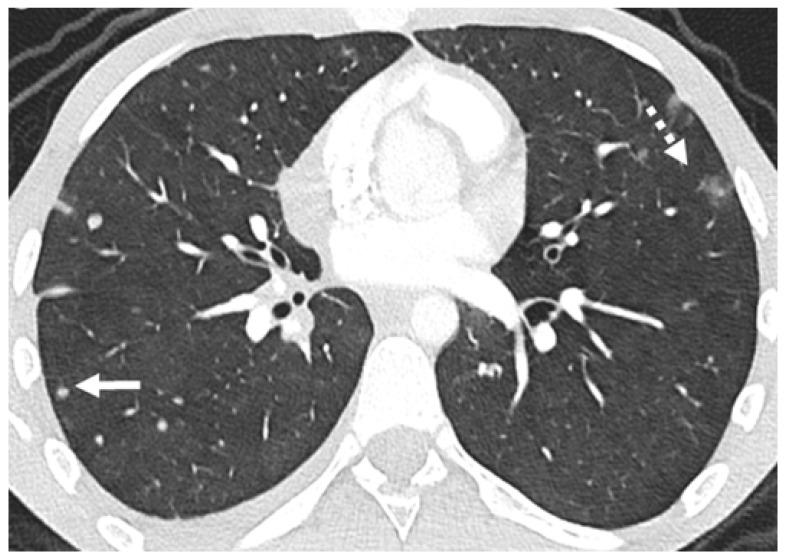

Osteosarcoma, a primary bone malignancy in children and adolescents, frequently metastasizes to the lungs, contributing significantly to morbidity and mortality. At diagnosis, 15-20% of patients present with detectable lung metastases. Chest computed tomography (CT) is vital for the early detection and monitoring of these metastases. Lung involvement typically presents as multiple nodules of varying sizes and can include atypical features such as cavitation, cystic lesions, ground-glass halos, intravascular tumor thrombi, and endobronchial disease. Pleural metastasis often occurs alongside pulmonary disease, and complications like spontaneous pneumothorax may arise. Additional findings may include thoracic lymphadenopathy, cardiac tumor thrombus, and chest wall deposits. Familiarity with these imaging patterns is essential for radiologists to ensure timely diagnosis and effective management. This review highlights the critical role of chest CT in detecting and characterizing osteosarcoma metastasis.

骨肉瘤是儿童和青少年常见的原发性骨恶性肿瘤,常转移至肺部,对发病率和死亡率有显著影响。在诊断时,15%至20%的患者出现可检测到的肺转移。胸部计算机断层扫描(CT)对于这些转移灶的早期检测和监测至关重要。肺部受累通常表现为大小不一的多个结节,可包括一些非典型特征,如空洞形成、囊性病变、磨玻璃晕、血管内肿瘤血栓和支气管内病变。胸膜转移常与肺部疾病同时发生,可能出现自发性气胸等并发症。其他表现可能包括胸内淋巴结肿大、心脏肿瘤血栓和胸壁转移灶。放射科医生熟悉这些影像学表现对于确保及时诊断和有效治疗至关重要。本综述强调了胸部CT在检测和鉴别骨肉瘤转移方面的关键作用。